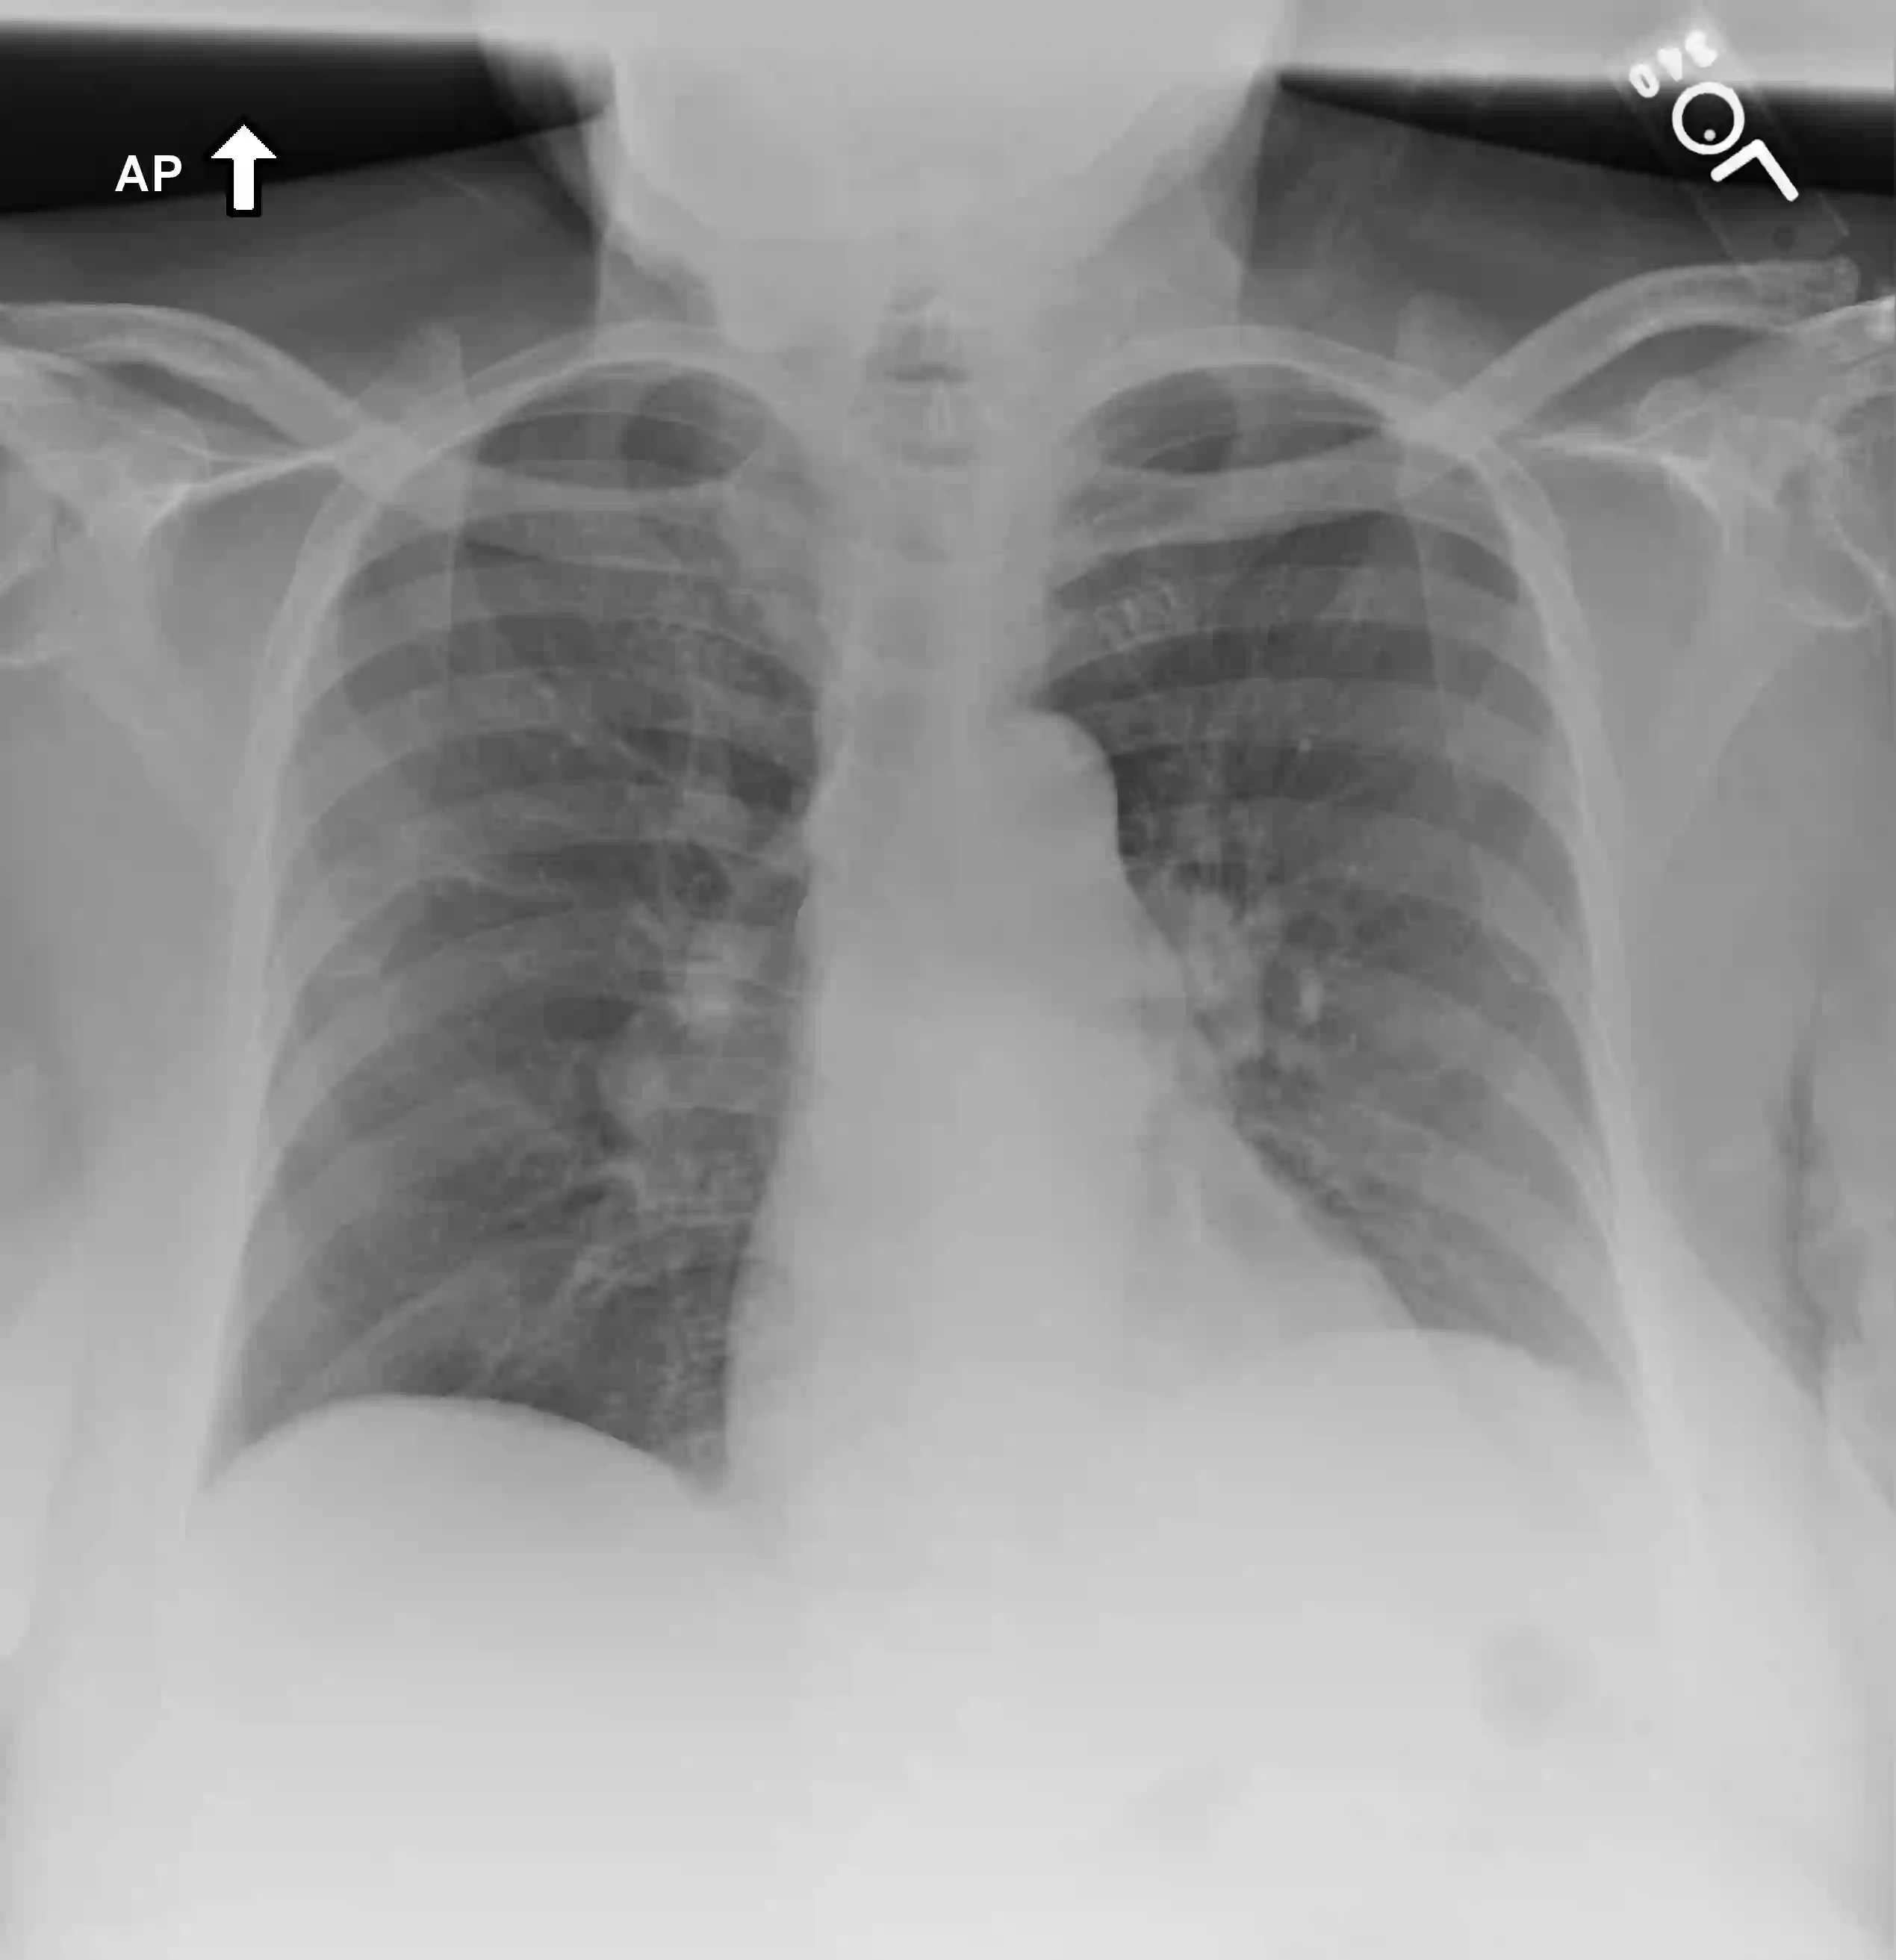

We introduce a novel Region-based contrastive pretraining for Medical Image Retrieval (RegionMIR) that demonstrates the feasibility of medical image retrieval with similar anatomical regions. RegionMIR addresses two major challenges for medical image retrieval i) standardization of clinically relevant searching criteria (e.g., anatomical, pathology-based), and ii) localization of anatomical area of interests that are semantically meaningful. In this work, we propose an ROI image retrieval image network that retrieves images with similar anatomy by extracting anatomical features (via bounding boxes) and evaluate similarity between pairwise anatomy-categorized features between the query and the database of images using contrastive learning. ROI queries are encoded using a contrastive-pretrained encoder that was fine-tuned for anatomy classification, which generates an anatomical-specific latent space for region-correlated image retrieval. During retrieval, we compare the anatomically encoded query to find similar features within a feature database generated from training samples, and retrieve images with similar regions from training samples. We evaluate our approach on both anatomy classification and image retrieval tasks using the Chest ImaGenome Dataset. Our proposed strategy yields an improvement over state-of-the-art pretraining and co-training strategies, from 92.24 to 94.12 (2.03%) classification accuracy in anatomies. We qualitatively evaluate the image retrieval performance demonstrating generalizability across multiple anatomies with different morphology.